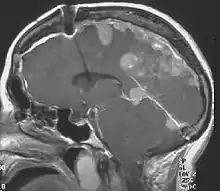

Neurofibromatosis type II (also known as MISME syndrome – multiple inherited schwannomas, meningiomas, and ependymomas) is a genetic condition which may be inherited or may arise spontaneously. The main manifestation of the condition is the development of bilateral benign brain tumors in the nerve sheath of the cranial nerve VIII, which is the "auditory-vestibular nerve" that transmits sensory information from the inner ear to the brain. Besides, other benign brain and spinal tumors occur. Symptoms depend on the presence, localisation and growth of the tumor(s). Many people with this condition also experience visual problems. Neurofibromatosis type II (NF2 or NF II) is caused by mutations of the "Merlin" gene,[1] which seems to influence the form and movement of cells. The principal treatments consist of neurosurgical removal of the tumors and surgical treatment of the eye lesions. Historically the underlying disorder has not had any therapy due to the cell function caused by the genetic mutation.

The so-called acoustic neuroma of NF2 is in fact a schwannoma of the nervus vestibularis, or vestibular schwannoma. The misnomer of acoustic neuroma is still often used. The vestibular schwannomas grow slowly at the inner entrance of the internal auditory meatus (meatus acousticus internus). They derive from the nerve sheaths of the upper part of the nervus vestibularis in the region between the central and peripheral myelin (Obersteiner-Redlich-Zone) within the area of the porus acousticus, 1 cm from the brainstem.